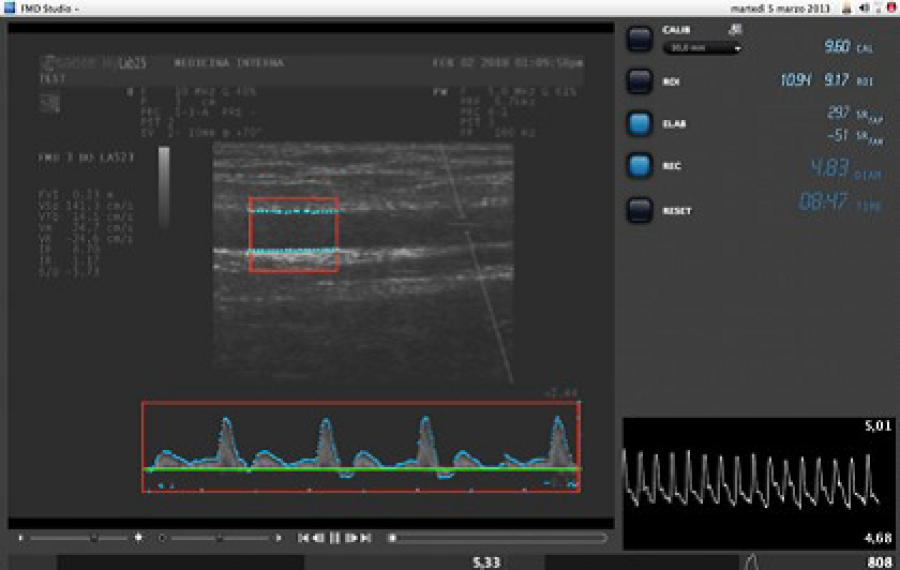

Flow Mediated Dilation

Flow Mediated Slowing